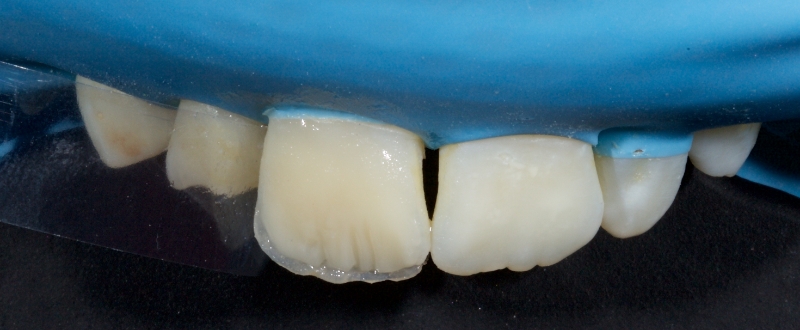

Due to its inherent translucency, the composite resin is limited in its opaquing ability, especially in thin sections. Specialized opaquers must be employed when masking discoloration to increase value and decrease chroma.

- Apply an even, homogenous layer of the opaquer to avoid the appearance of spotting (theshine through of highly opaque or discolored areas in the final restoration).

The opaquer is usually applied with a No. 3 artist’s brush or Tokuyama No. 24 brush. Initially, the brush is loaded, which means it is dipped into a composite modeling resin (e.g., BISCO modeling resin). Loading the brush leads to a more even application of the opaquer. Excess modeling resin is removed by wiping the brush on gauze. The opaquer is then applied in multiple thin, even layers polymerizing each layer before the next application. The opaquer is applied from gingival to incisal, taking care to avoid pooling. Usually, 3-5 layers are required, according to a 2013 paper by J.S. An. - According to Felippe and Baratieri, care should be taken to allow a minimal thickness of 0.4 mm for the layering of the resin veneer after the opaquer application is completed.